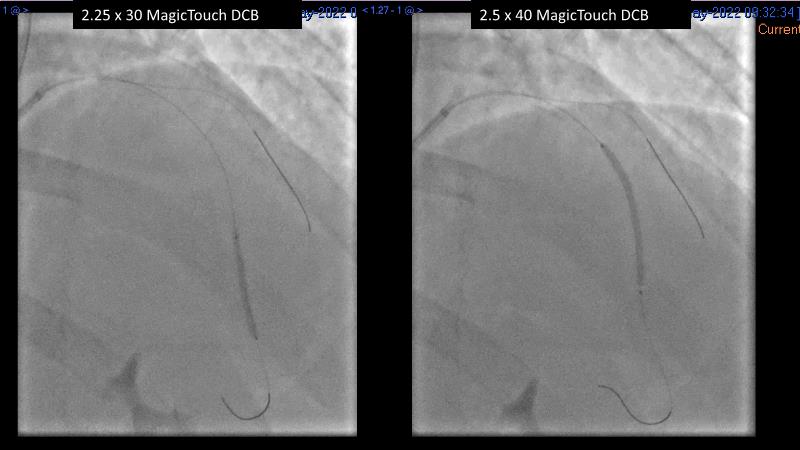

Consult this session to understand the technology and scientific evidence of the novel sirolimus drug-coated balloon, to learn its utility for PCI in a variety of lesion and patient subsets and to understand the evidence and outcomes in real-world patients.

- To learn the utility of the DCB for PCI in a variety of lesion and patient subsets